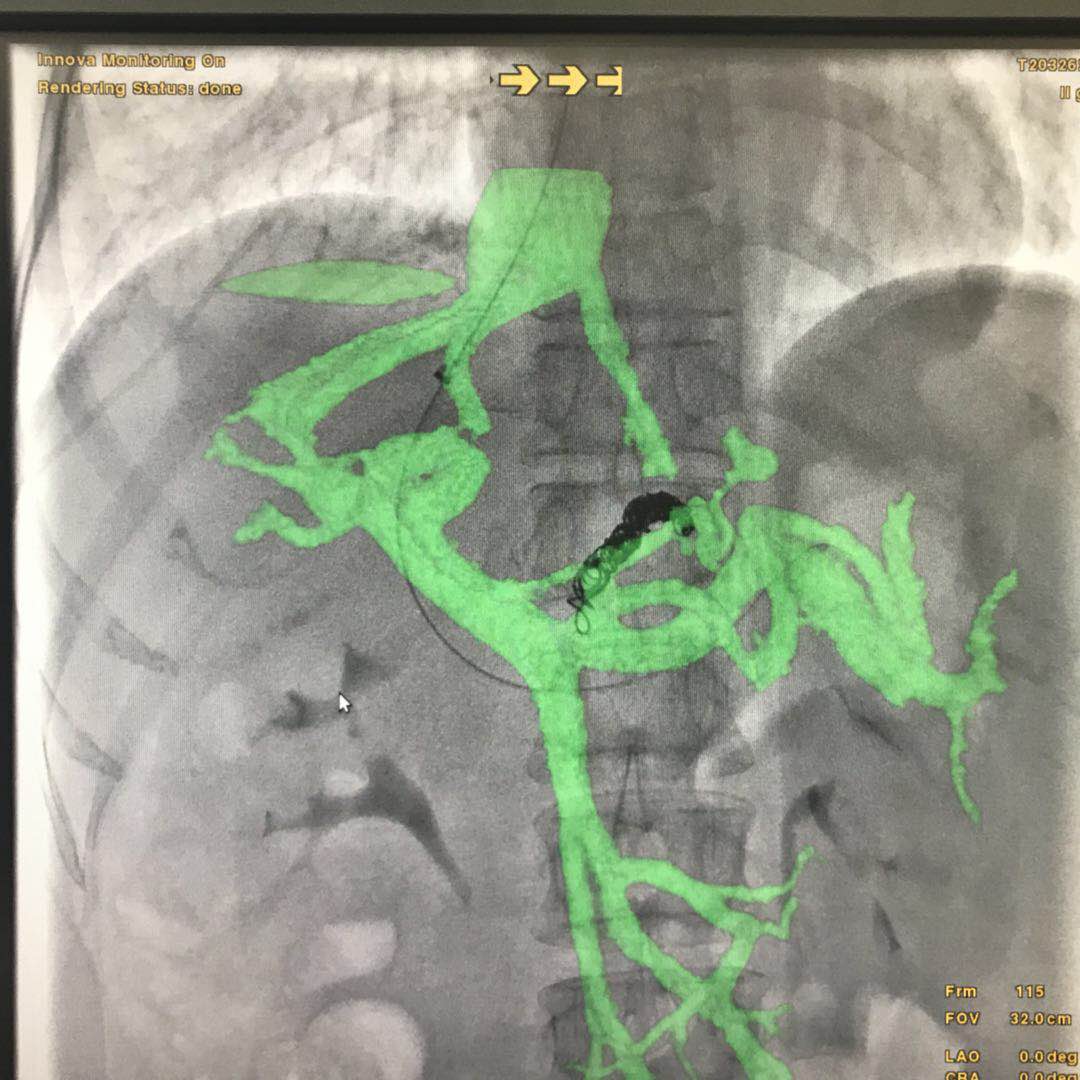

要想安全、准确地完成TIPSS手术,对术者的技术要求非常高。手术前,术者要通过术前的影像学资料:上腹部增强CT或MRI非常明确肝静脉和门静脉的解剖位置关系:即穿刺针进入到肝静脉后,术者要在头脑中把影像学中两者的前后左右位置关系转换成进针角度,把两者的距离远近转换成穿刺深度。如果对角度把握不准确,则很难穿中门静脉;如果对距离远近估计有误,穿刺深度不够时很难穿中门静脉,穿刺过深时,一旦穿刺到肝外门静脉,则容易出现术中腹腔大出血,严重威胁患 的呢?操作步骤非常简单:1、获得患者术前上腹部CTA/MRA图像,以此为基础,将患者的椎体、肝静脉和门静脉生长出来;;2、在透视下,用骨性标志和术中患者的实际位置进行配准对位,这样生长出来的肝静脉和门静脉的模型与患者实际的血管解剖部位自然也就配准了。不仅如此,在导丝进入肝静脉后我们还可以将肝静脉的模型和患者再次进行精准对位3、在透视下,我们可以直接按照智能路图来对着门静脉的方向进行穿刺在此过程中,只要患者相对于导管床的位置不变,无论机架角度和导管床的位置如何变换,智能路图的影像与机架和导管床都是联动的,无需重新对位置,不用担心模型与实际血管错位,如此大大方便了医生从各个角度观察门静脉的走形和位置,及时调整穿刺针的角度和深度。 本周在河南某医院进行了影像融合下引导TIPSS手术,大大提高了手术精度,最大程度地降低了手术风险,减少了操作时间,提高了术者信心。手术图像详见下图: